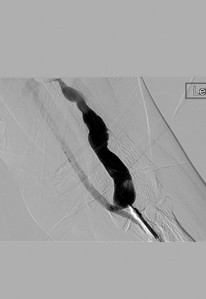

Fistulogram following 1st pass with an AngioJet DVX catheter (NB: no thrombolytics used).

Fistulogram post 2nd pass with DVX catheter. A further mid-AVF stenosis has been identified.

Stenting of the cephalic arch and cephalic fistula was required due to significant elastic recoil following angioplasty of these strictures.

An anastomotic stricture was also identified.

Post angioplasty of anastomotic stricture.